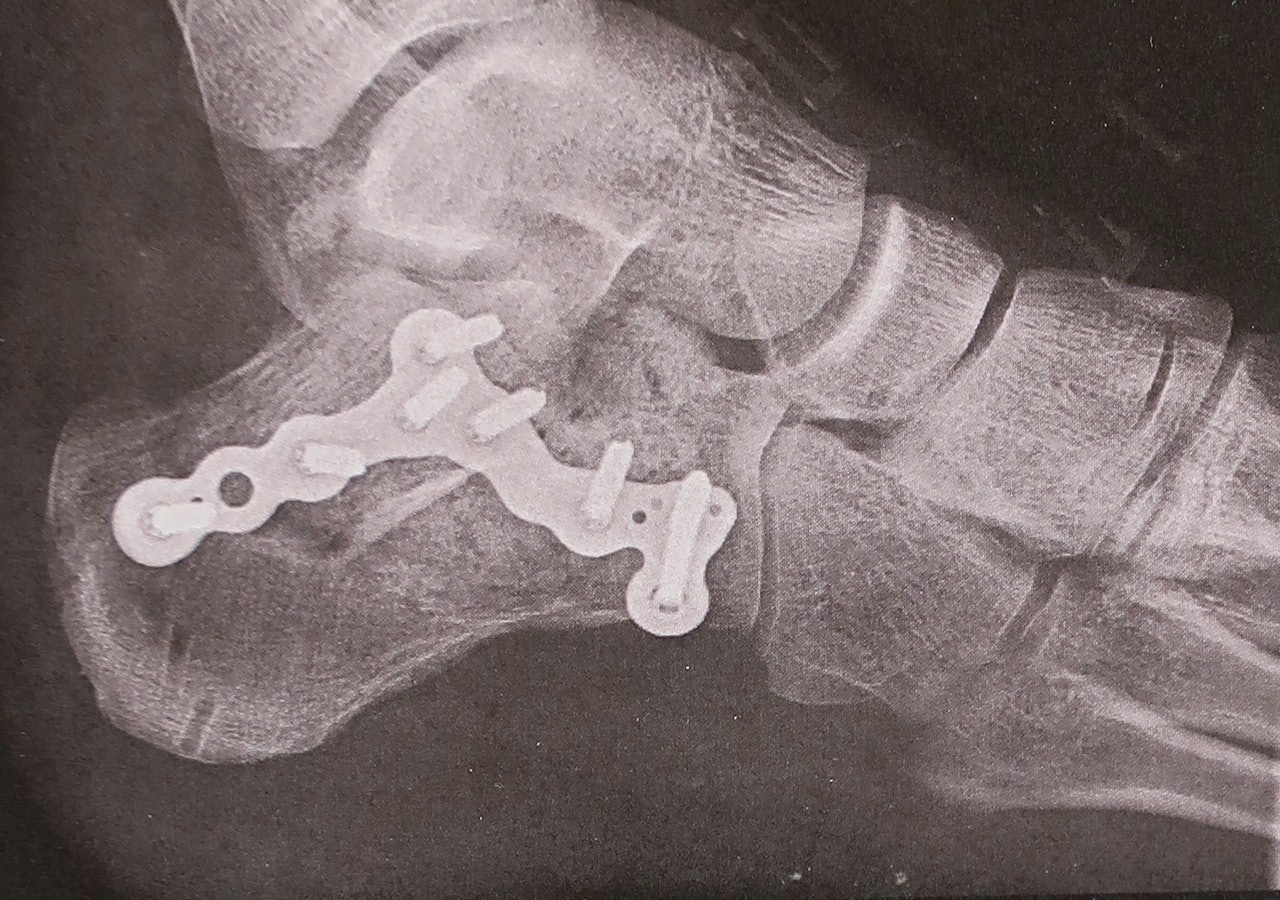

Les også: En sommer med ankelbrudd – fortalt av en av de uheldige.